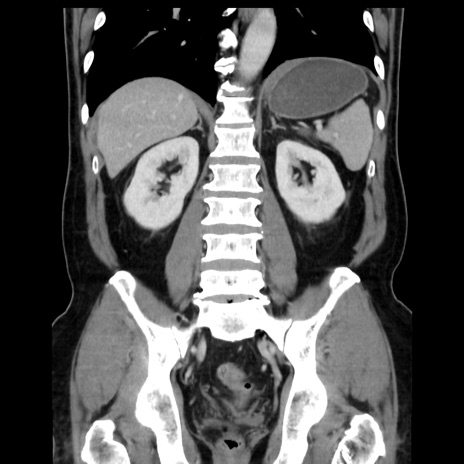

症例16(冠状断像)

【現病歴】 約1ヶ月前より間欠的に腹痛と嘔吐あり、当院消化器内科を受診したところCTで多発する肝臓のLDAを指摘され、精査中であった。以降は消化器症状は安定していたが、2日前より嘔気と腹痛があり、同日より排便・排ガスが消失した。改善認めず、 本日、救急外来を受診した。